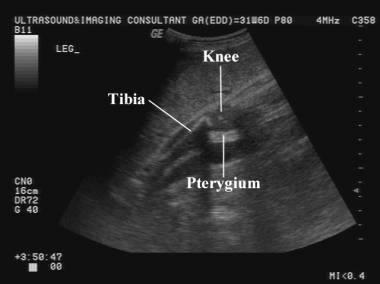

What is Pterygium?

webbing across joints

Pterygium

webbing across joints